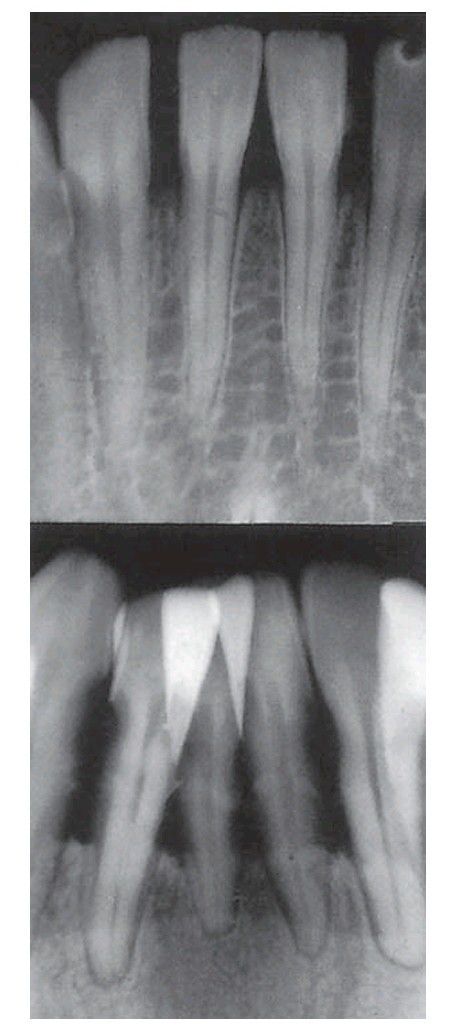

Early and severe horizontal bone loss in advanced chronic adult periodontitis.